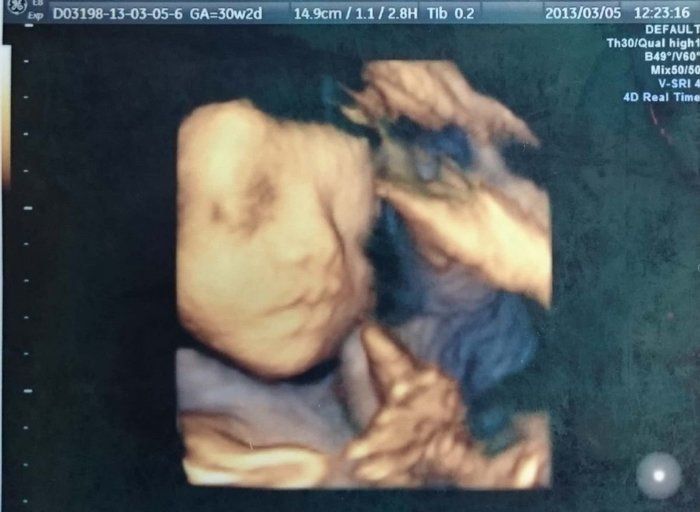

たかこさんの妊娠30週目のエコー写真 再びの3D写真。今見ると、すでに面影あり

見たいと言ったら見せてくれた3Dエコー。表情がしっかりと分かります。その当時は、「赤ちゃんの人形みたいに見えて、そんなに特徴が分からないな」と思いましたが、今見てみると、息子の寝顔そのまま。面影がかなりあります。私のおなかも大きくなり、歩くペースも遅くなっていた頃でしたが、先生に確認をして隣県へ2泊3日のマタニティ旅行をしました。